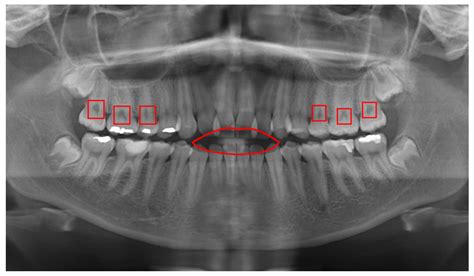

When you step into a dental office for a comprehensive examination, your dentist often suggests advanced imaging to get a complete picture of your oral health. One of the most common and vital tools in modern dentistry is the Panoramic Dental X Ray. Unlike standard bitewing or periapical X-rays that focus on one or two teeth, this imaging technique captures the entire mouth in a single, sweeping image. This includes the upper and lower jaws, all the teeth, the temporomandibular joints (TMJ), and even the surrounding sinus structures, providing a holistic view that is indispensable for accurate diagnosis and treatment planning.

The Panoramic Dental X Ray utilizes a specialized machine called an orthopantomogram (OPG). During the procedure, the X-ray tube and the digital sensor rotate in a semicircular motion around your head, capturing a continuous image of your dental anatomy. Because the human jaw is curved, the machine is calibrated to track this arc, ensuring that all dental structures remain in focus throughout the rotation.

This technology is revolutionary because it eliminates the need for placing multiple small sensors inside your mouth, which can be uncomfortable for patients with a sensitive gag reflex. By capturing the entire maxillofacial region, dentists can identify conditions that might otherwise remain hidden beneath the gum line or deep within the jawbone.

The applications for Panoramic Dental X Ray imaging are vast. Orthodontists frequently use these images to map the growth of teeth in adolescents and ensure there is enough space for proper alignment. Oral surgeons rely on them to visualize the proximity of wisdom teeth to the nerves in the lower jaw, which is critical for planning extractions safely.

Furthermore, these scans are vital in diagnosing jaw joint disorders. By observing the TMJ through the panoramic image, dentists can assess if there is structural degradation or uneven wear that might be contributing to facial pain or headaches. The ability to see the sinuses is also beneficial, as it allows the dentist to distinguish between dental pain and referred pain caused by sinus congestion or infection.